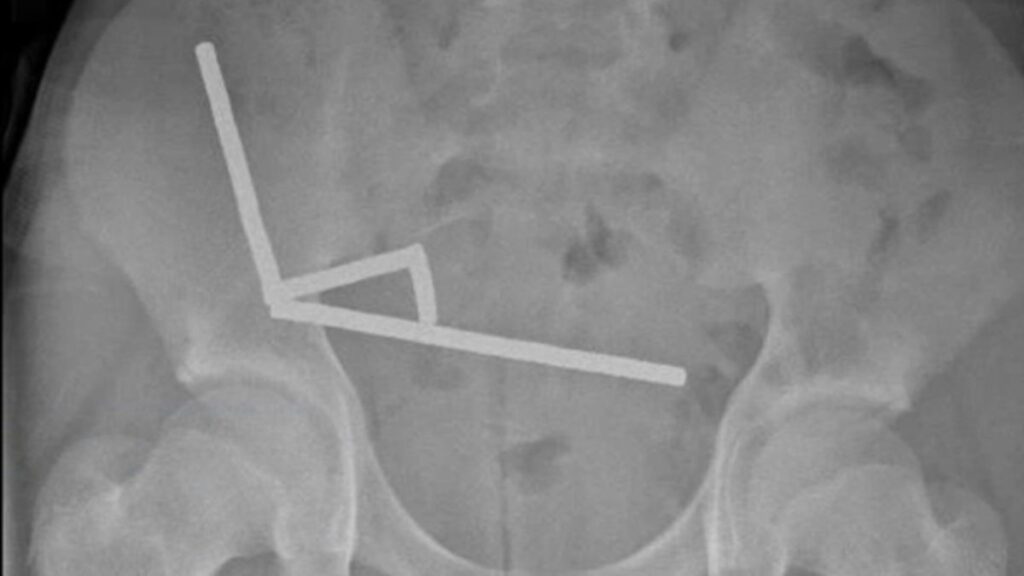

Usando um raio X, os médicos visualizaram quatro cadeias lineares em partes separadas do intestino do menino.

Durante a cirurgia, as cadeias foram encontradas em seções separadas do intestino delgado e do ceco. Ao se comprimirem, elas causavam a morte de diversas áreas do tecido por falta de sangue, no que é conhecido como necrose por pressão.